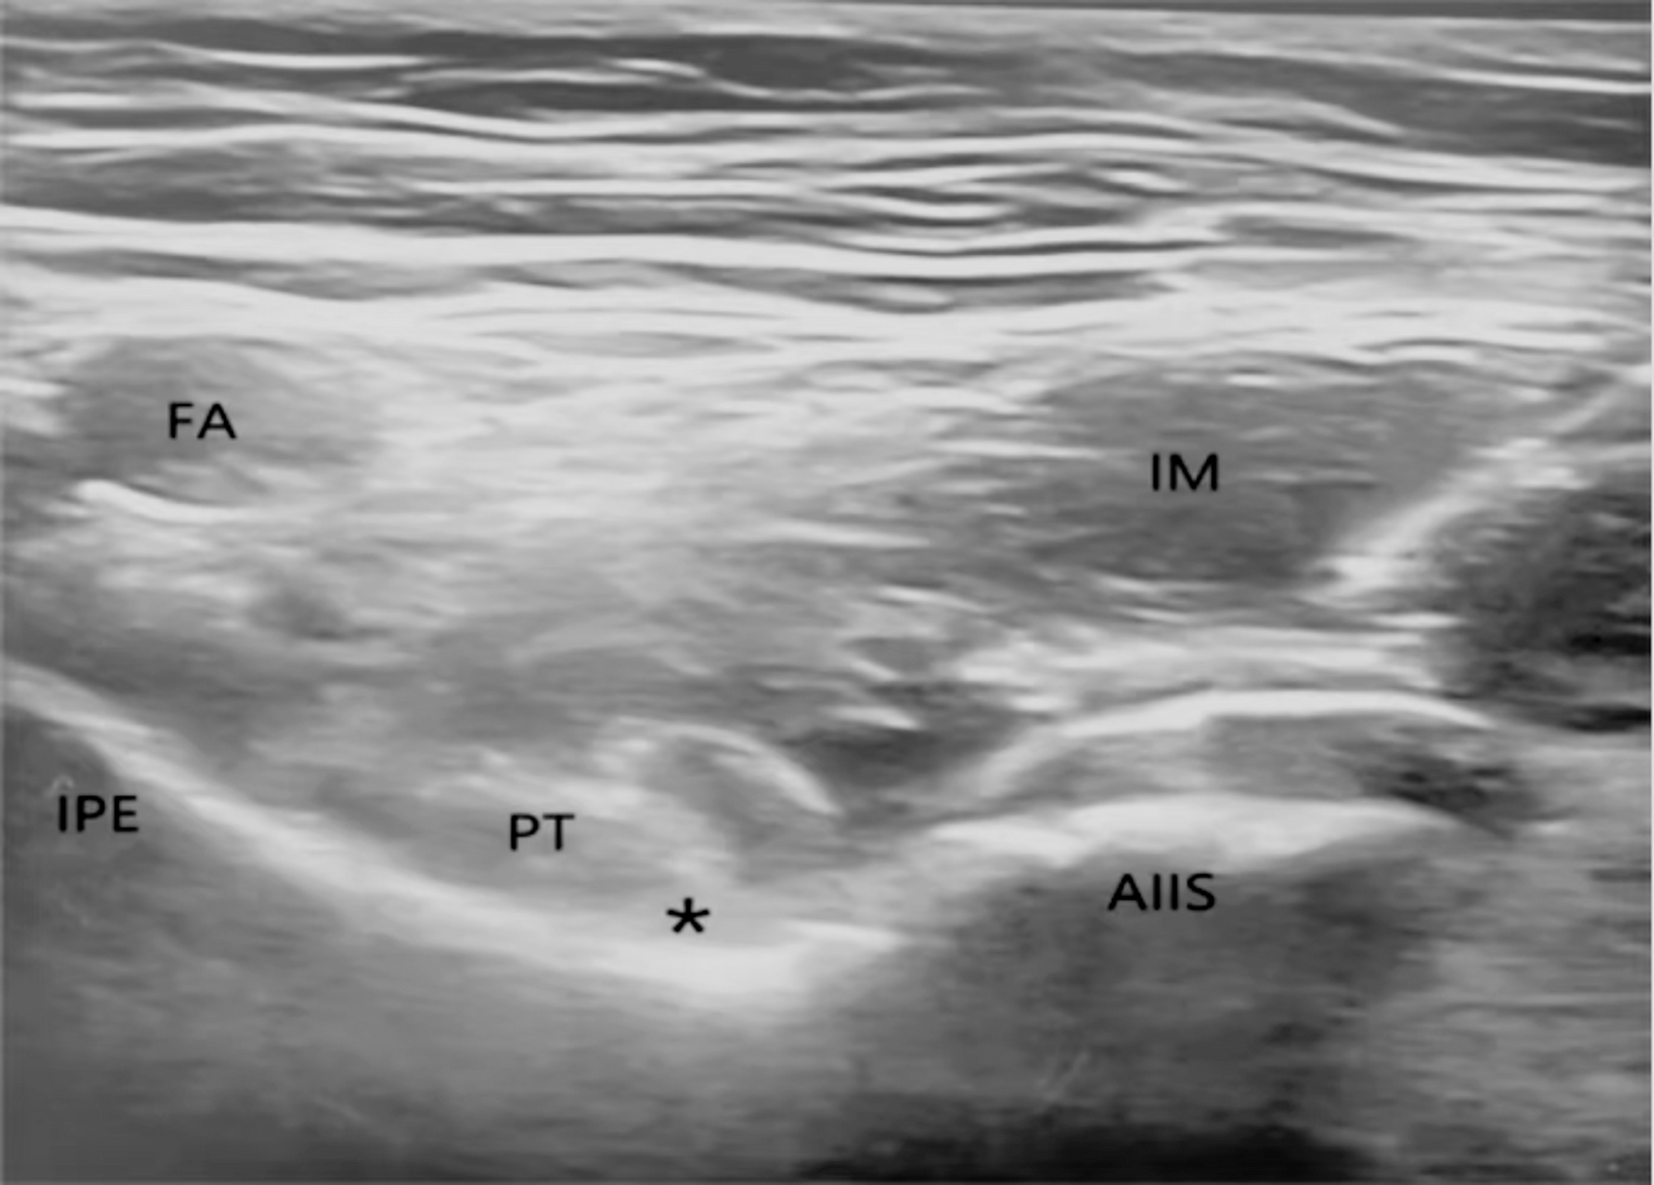

Ultrasound image of pericapsular nerve group block. AIIS, anterior inferior iliac spine; FA, femoral artery; IM, iliac muscle; IPE, iliopubic eminence; PT, psoas muscle tendon; asterisk indicates target for local anesthetic.